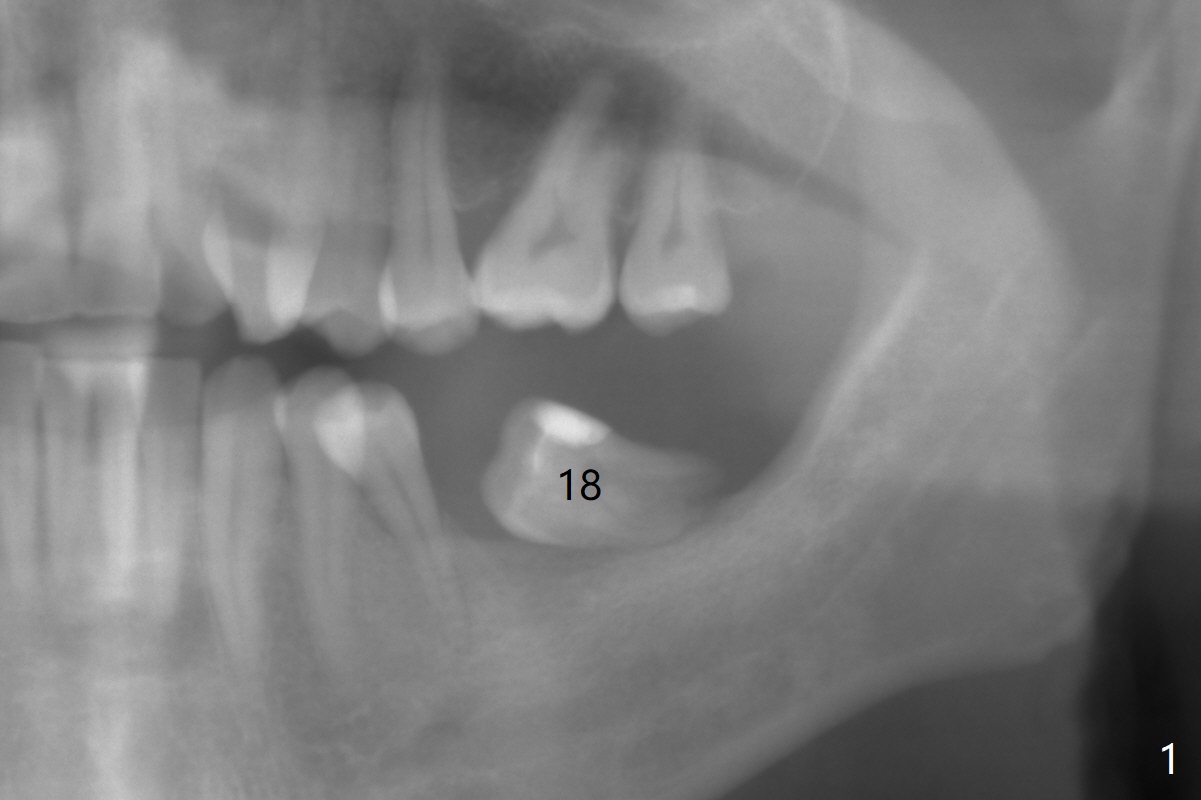

A 43-year-old man has poor dentition on the left: 1st molar missing, 2nd molar mesial inclination (Fig.1) and 2nd bicuspid lingual tilt (Fig.2). The latter is nonfunctional (Fig.3 (linguoposterior view). Two molar implants will be placed in a position so that their crowns will be in cross bite (Fig.4,5), the same occlusal scheme as the teeth #21 and 22. When these implants osteointegrate, the provisional crowns (Fig.6 P) will be supraocclusal so that there is clearance (*) for #20 to upright orthodontically (Fig.7-9). Moreover, these implants will be used anchorage as well as #21 and 22. Panoramic X-ray (Fig.1) and CBCT (Fig.10-12) show limited bone height at the sites of #18 and 19. It appears that 5x8 and 5.9x6 mm implants are appropriate with ridge reduction at #19.